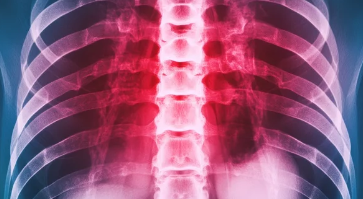

늑골 골절, 숨 쉴 때마다 고통... 방치하면 평생 후유증 남을 수도!

넘어지거나 부딪히는 등 강한 충격을 받으면 늑골(갈비뼈) 골절이 발생할 수 있습니다. 늑골 골절은 숨을 쉴 때마다 극심한 통증을 유발하며, 심한 경우 폐나 다른 장기 손상으로 이어질 수 있는 위험한 질환입니다.

늑골 골절은 단순히 뼈가 부러지는 것에 그치지 않고, 다양한 후유증을 남길 수 있습니다.

2. 호흡 곤란: 숨 쉴 때마다 답답함

늑골 골절은 폐 기능 저하로 이어져 호흡 곤란을 유발할 수 있습니다. 특히 다발성 늑골 골절이나 흉곽 골절의 경우 흉벽의 안정성이 떨어져 호흡 운동이 제한되고, 폐렴, 무기폐 등 합병증 발생 위험이 높아집니다.

호흡 곤란은 일상생활에 큰 지장을 주고, 심한 경우 생명을 위협할 수도 있습니다. 늑골 골절 후 호흡 곤란 증상이 나타난다면 즉시 병원을 찾아 응급 처치를 받아야 합니다.